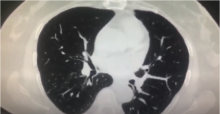

This video demonstrates an anatomic variation encountered during a uniportal VATS right lower lobectomy - the absence of right segment arterial branch six.